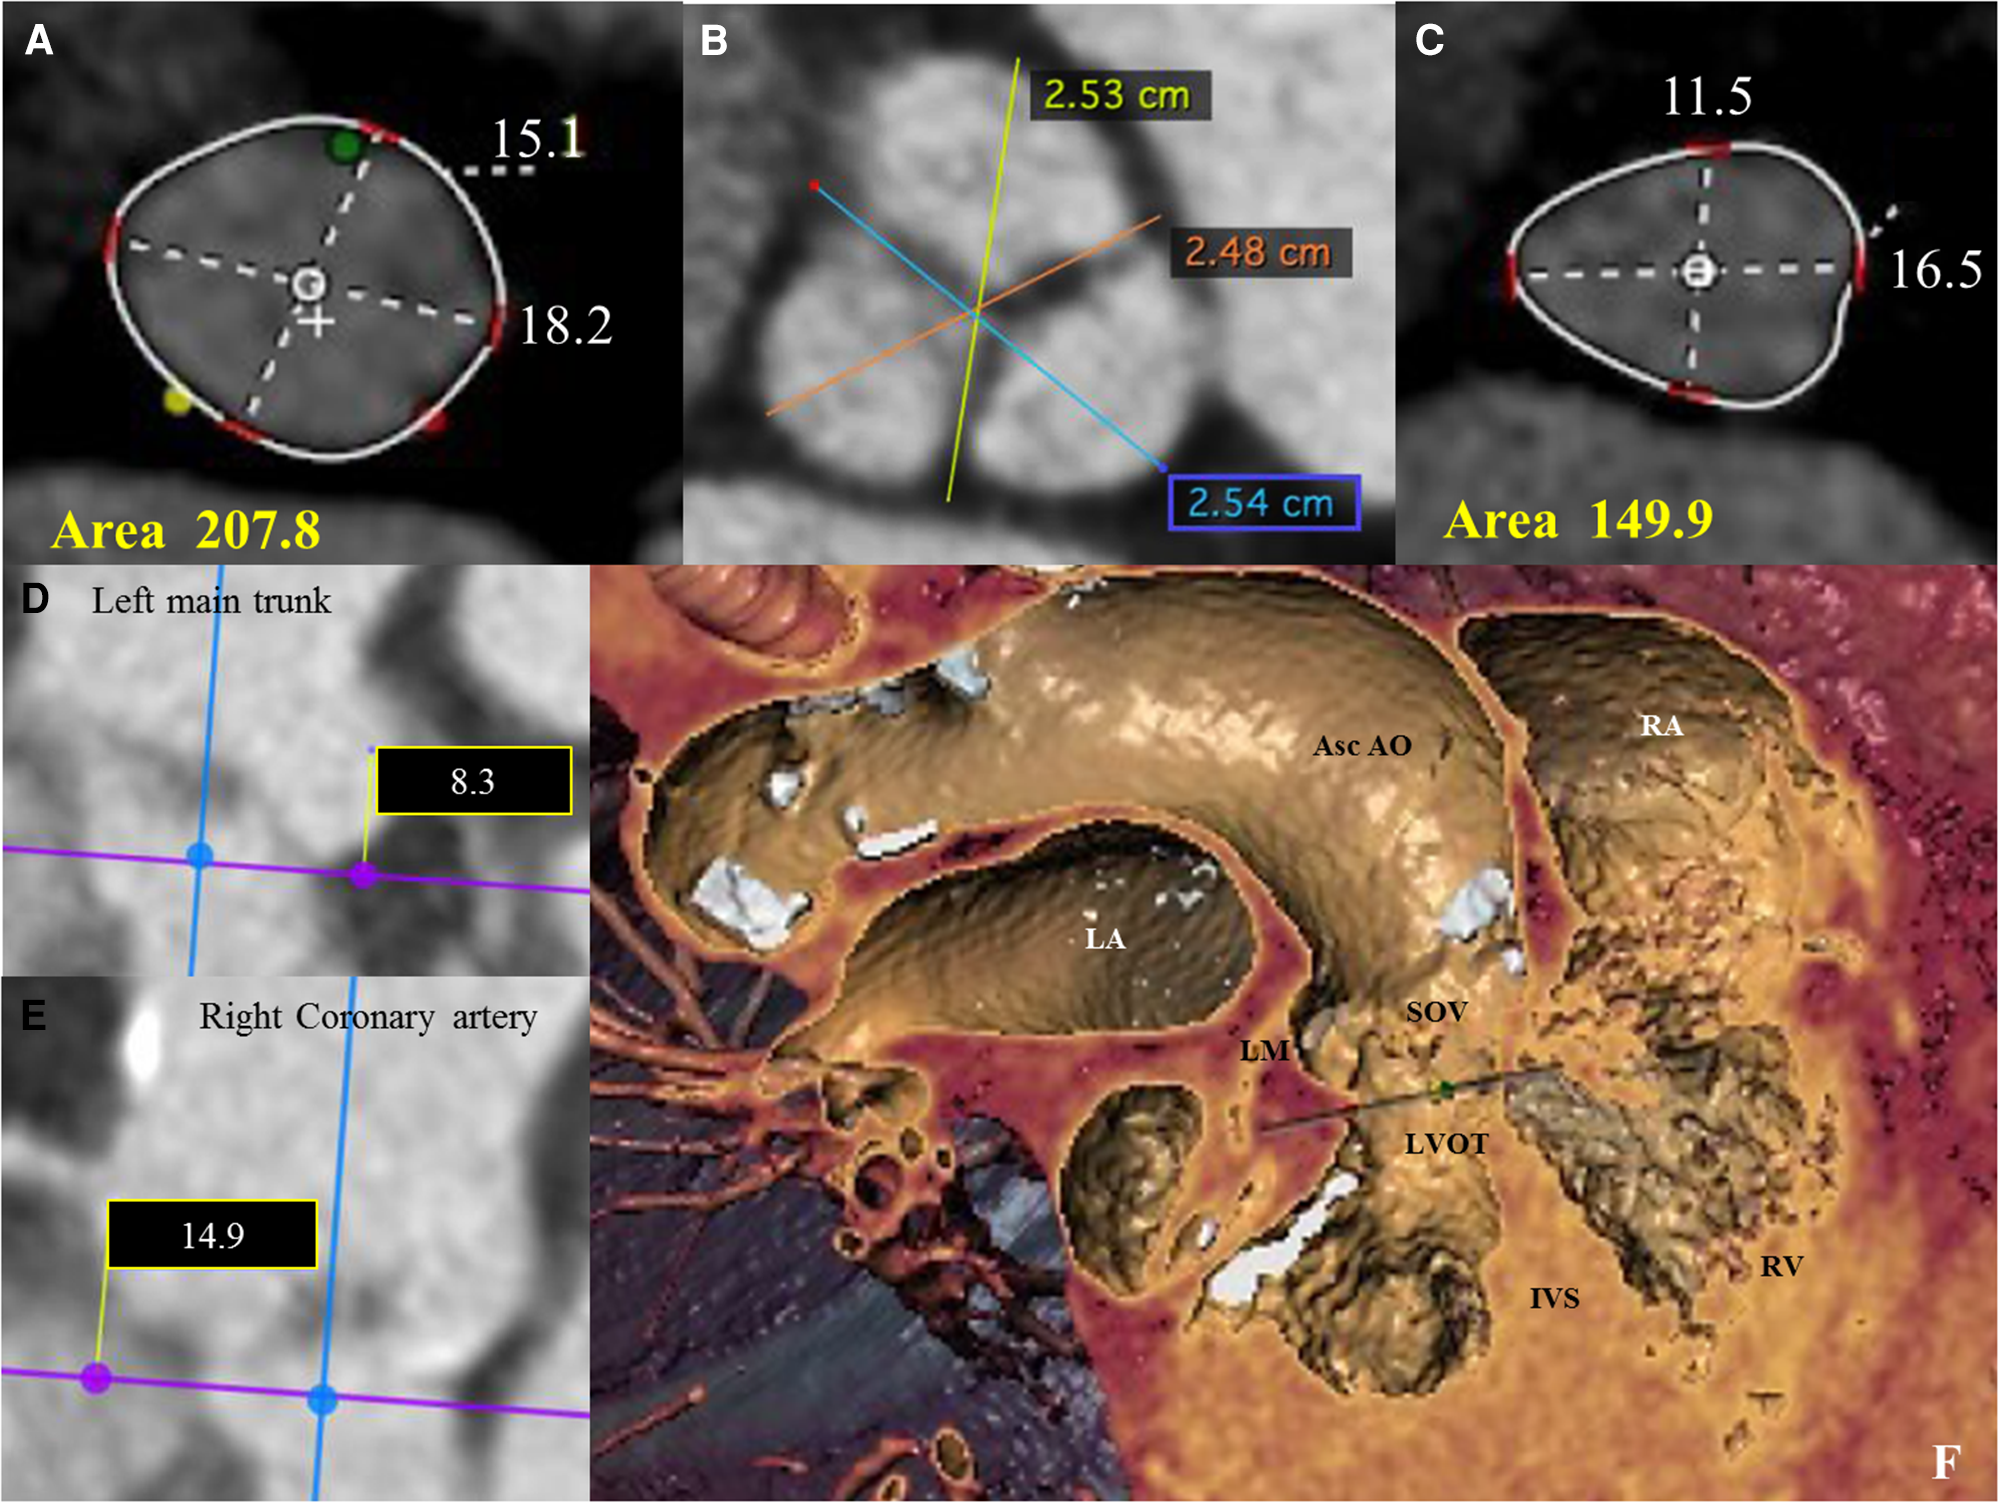

Figure 2

(A) Pre-operative thoraco-abdominal computed tomography (CT) images were analyzed using 3mensio Structural Heart software (Pie Medical Imaging, Netherlands): the aortic annulus perimeter was 51.7 mm (minor annulus diameter 15.1 mm, major annulus diameter 18.2 mm) and the area was 207,8 mm2. (B) Pre-operative thoraco-abdominal CT images showed a tricuspid aortic valve without significant valvular calcifications (images reconstructed with OsiriX DICOM Viewer Pixmeo SARL, Switzerland). (C) Pre-operative thoraco-abdominal CT images showed a LVOT perimeter of 45.3 mm with elliptical shape (minor annulus diameter 11.5 mm, major annulus diameter 16.5 mm) and an area of 149,9 mm2 (images reconstructed with 3mensio Structural Heart software). (D and E) CT images showing the distance from the virtual basal ring (VBR) to left main trunk of 8.3 mm (see D) and to the right coronary artery of 14.9 mm (see E). (F) Pre-operative thoraco-abdominal CT images showing the heart chambers and the ascending aorta according to the ‘double oblique virtual reality’ reconstruction with 3mensio Structural Heart software. Asc Ao, Ascending Aorta; IVS, interventricular septum; LM, left main coronary trunk; LA, left atrium; LVOT, left ventricular outflow tract; RA, right atrium; RV, right ventricle.